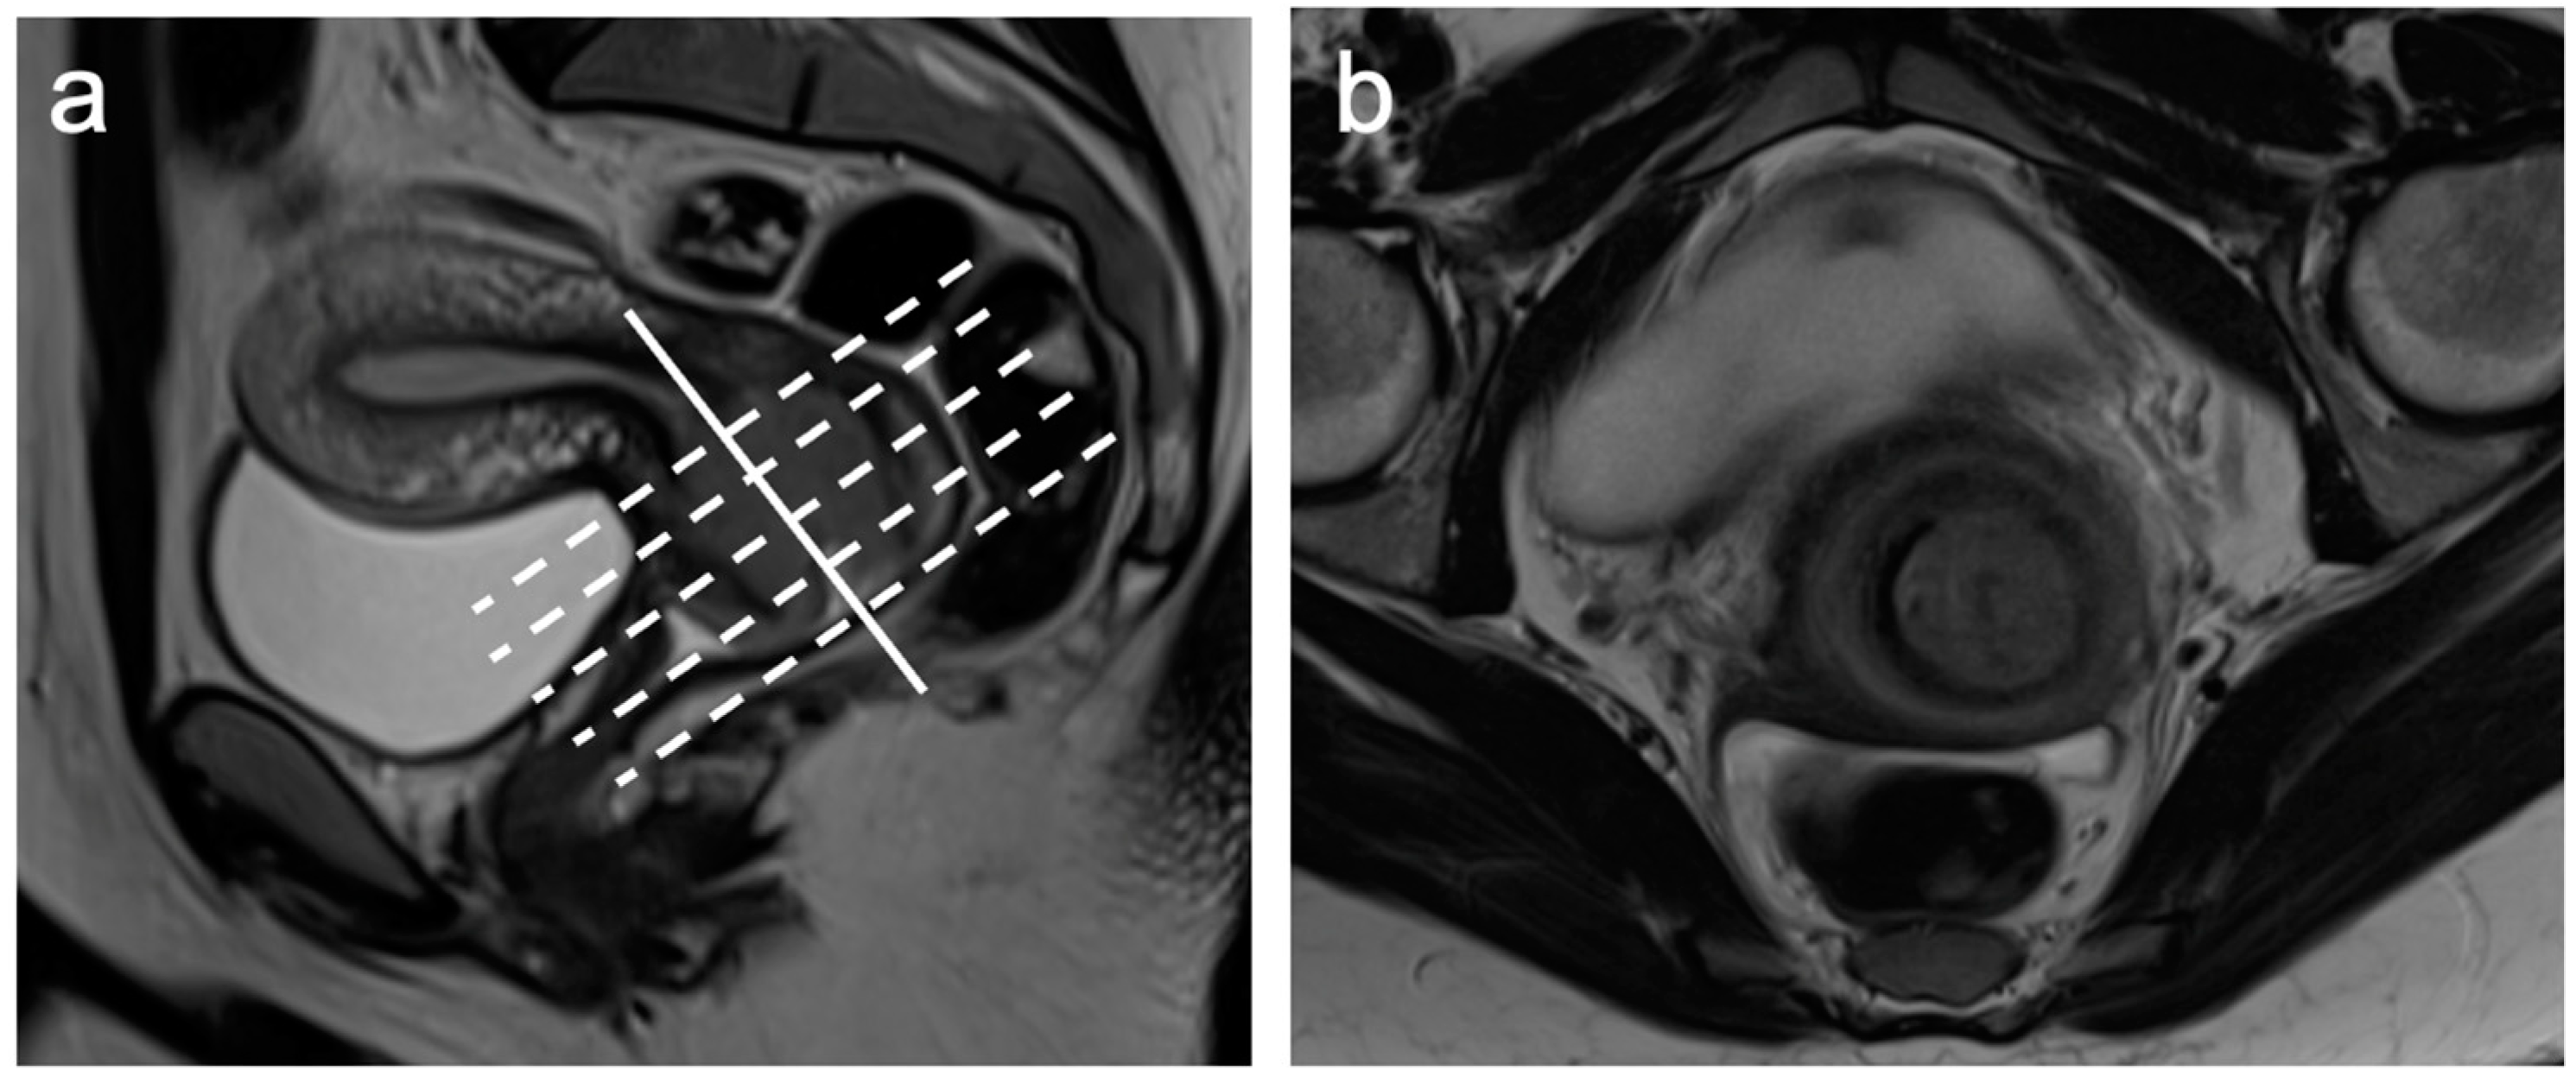

| Small FOV Sagittal T2WI | Accurate tumour size, local staging (e.g., vaginal, bladder, rectal invasion) |

| Small FOV Axial oblique T2WI | Local staging, parametrial and pelvic sidewall involvement |

- McEvoy, S.H.; Nougaret, S.; Abu-Rustum, N.R.; Vargas, H.A.; Sadowski, E.A.; Menias, C.O.; Shitano, F.; Fujii, S.; Sosa, R.E.; Escalon, J.G.; et al. Fertility-sparing for young patients with gynecologic cancer: How MRI can guide patient selection prior to conservative management. Abdom. Radiol. 2017, 42, 2488–2512, Erratum in Abdom. Radiol. 2017, 42, 2966–2973. [Google Scholar]

- Halaska, M.; Robova, H.; Pluta, M.; Rob, L. The role of trachelectomy in cervical cancer. Ecancermedicalscience 2015, 9, 506. [Google Scholar] [CrossRef]

- Rockall, A.G.; Qureshi, M.; Papadopoulou, I.; Saso, S.; Butterfield, N.; Thomassin-Naggara, I.; Farthing, A.; Smith, J.R.; Bharwani, N. Role of Imaging in Fertility-sparing Treatment of Gynecologic Malignancies. Radiographics 2016, 36, 2214–2233. [Google Scholar] [CrossRef] [PubMed]

- Noël, P.; Dubé, M.; Plante, M.; St-Laurent, G. Early cervical carcinoma and fertility-sparing treatment options: MR imaging as a tool in patient selection and a follow-up modality. Radiographics 2014, 34, 1099–1119. [Google Scholar] [CrossRef] [PubMed]